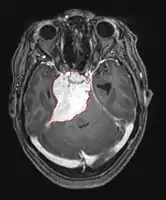

Imaging

- Benign Meningioma on MRI

- MRI

- Preferred imaging because it can show dural origin

- Dural tail sign seen in about two-thirds: characteristic marginal thickening that tapers peripherally along the dura

- Isointense on T1, hyperintense (usually homogeneously) on T2, strong enhancement with IV contrast